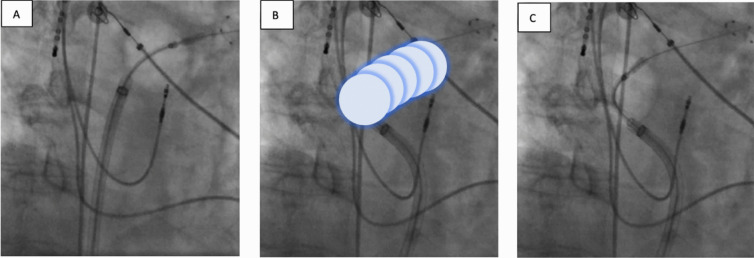

Background: Single-shot ablation systems are widely used for pulmonary vein isolation (PVI) in atrial fibrillation (AF). The use of novel pulsed-field ablation (PFA) systems enables ablation beyond PVI, such as left atrial roof ablation (LARA), which may improve outcomes in persistent AF.

Objective: This study aimed to compare the acute efficacy, feasibility, and safety of PVI combined with LARA using three different single-shot ablation systems in patients with persistent AF and left atrial enlargement undergoing their first AF ablation.

Methods: Consecutive patients undergoing PVI with LARA using cryoballoon or PFA systems were included. Baseline characteristics, procedural parameters, and complication rates were assessed.

Results: We included 125 patients with persistent AF and left atrial dilation, divided into cryoballoon (n = 65), pentaspline PFA (n = 30), and circular PFA (n = 30) groups. Acute PVI was achieved in 100% of veins. Fewer applications were required for LARA with cryoballoon vs. PFA (4 vs. 8 vs. 10, P < 0.001). Conduction block was confirmed in 95%, 100%, and 100% of patients (P = 0.421). Procedural times were longer with cryoballoon (87.0 vs. 64.0 vs. 68.0 min, P < 0.001), but fluoroscopy times were shorter (12.2 vs. 15.3 vs. 15.1 min, P = 0.002). Contrast medium use was higher in the cryoballoon group (P < 0.001). Adverse events were rare and predominantly minor, with three complications in the cryoballoon group and one in the PFA groups (P = 0.493).

Conclusion: All single-shot ablation systems demonstrated comparable efficacy and safety for PVI and LARA, with differences in procedural feasibility. Further and larger studies are needed.